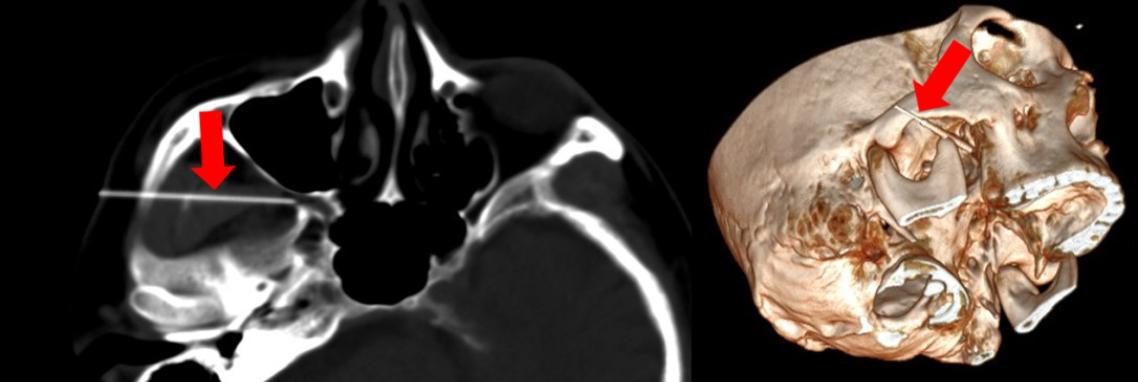

許一智解釋,首先會在病患頭部貼上磁導裝置,接著進行顱底CT掃描,以取得神經孔與周邊結構的精準影像,隨後將這些CT影像匯入超音波儀器中。當醫師把超音波探頭放在患者臉部並按下同步鍵後,超音波畫面便會即時顯示CT影像,兩者以一對一的方式同步呈現,醫師因此能同時看見即時的血管與軟組織位置,以及CT所呈現的骨性神經孔結構。

藉由這種融合影像,醫師能在畫面上直接標示目標神經孔(例如圓孔、卵圓孔),讓針尖得以沿著最佳、安全的路徑前進至治療位置。